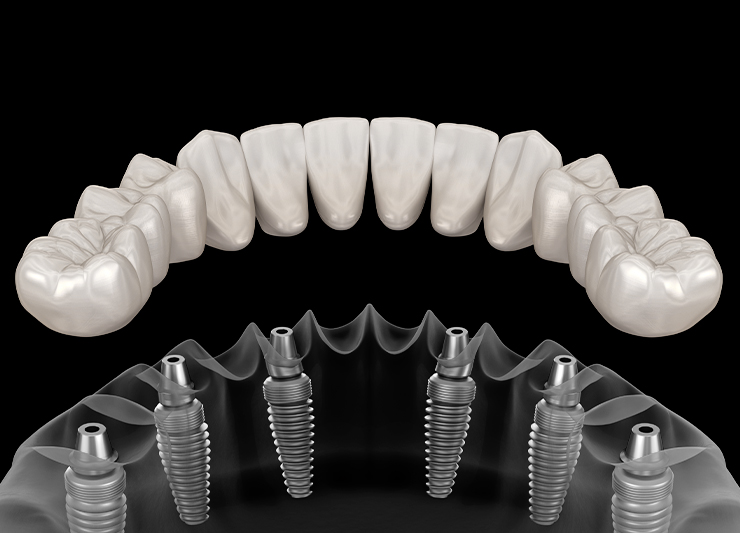

03 탈착식 임플란트 틀니

치아가 전혀 없을 때 임플란트를 2~6개 식립해 틀니를 더 편하게 만드는 방법입니다. 환자 스스로 탈착이 가능하고 관리가 용이합니다. 단점으로는 부속의 마모 및 잇몸 형태 변화에 따른 수리 교체 비용이 발생한다는 것 입니다.